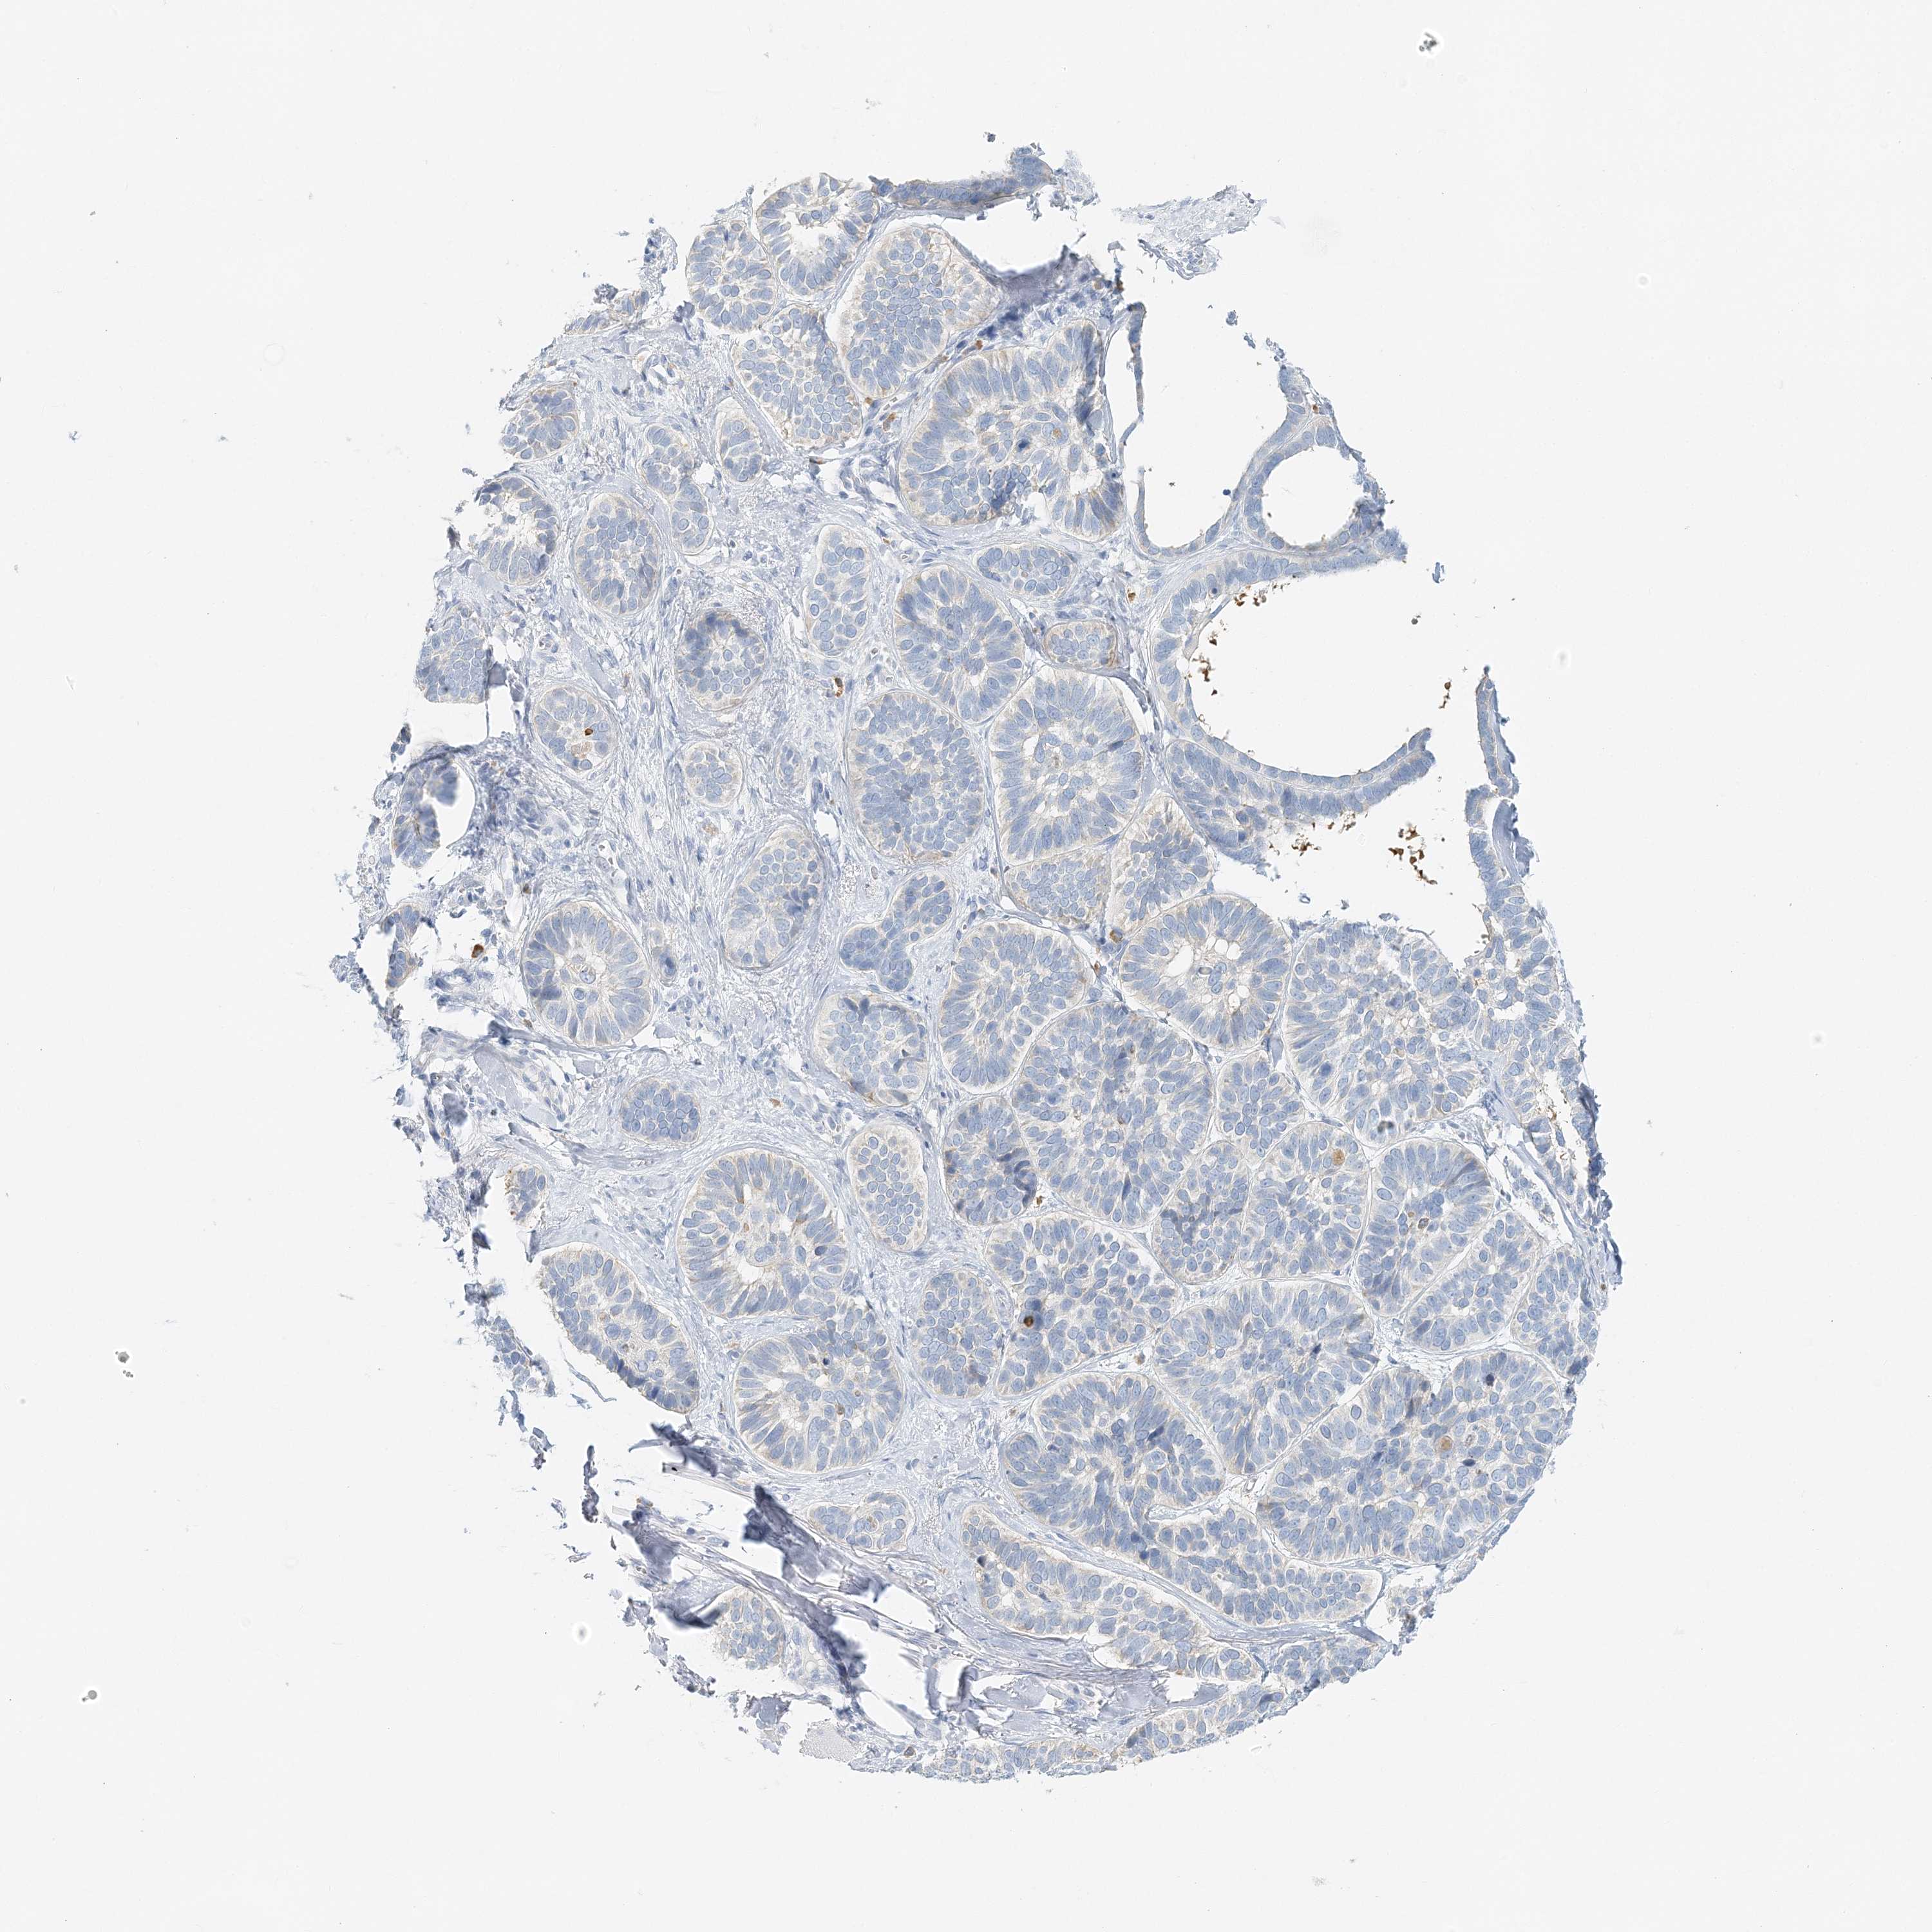

Basal cell and squamous cell cancer

SKIN CANCER - Protein expressioni

A mouse-over function shows sample information and annotation data. Click on an image to view it in a full screen mode. Samples can be filtered based on level of antibody staining by selecting one or several of the following categories: high, medium, low and not detected. The assay and annotation is described here.

Antibody stainingi

Antibody staining in the annotated cell types in the current human tissue is reported as not detected, low, medium, or high, based on conventional immunohistochemistry profiling in selected tissues. This score is based on the combination of the staining intensity and fraction of stained cells.

Each image is clickable and will lead to virtual microscopy that enables deeper exploration of all samples and also displays staining intensity scores, fraction scores and subcellular localization as well as patient and tissue information for each sample.

Antibody HPA035675

Staining

High

Medium

Low

Not detected

Intensity

Strong

Moderate

Weak

Negative

Quantity

>75%

75%-25%

<25%

None

Location

Nuclear

Cytoplasmic/membranous

Cytoplasmic/membranous,nuclear

Basal cell carcinoma